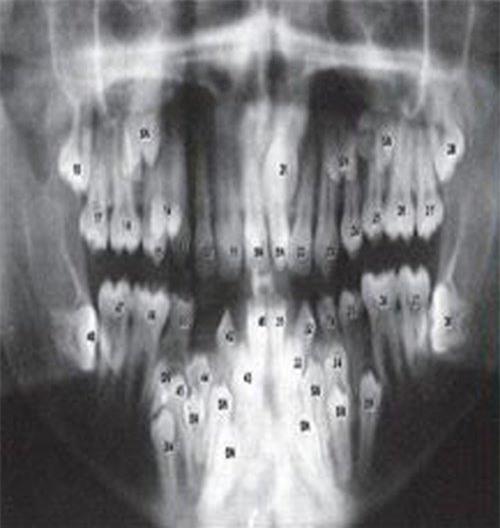

Bản phim X-quang cho thấy có vô số răng mọc trong miệng và không theo một trình tự nào